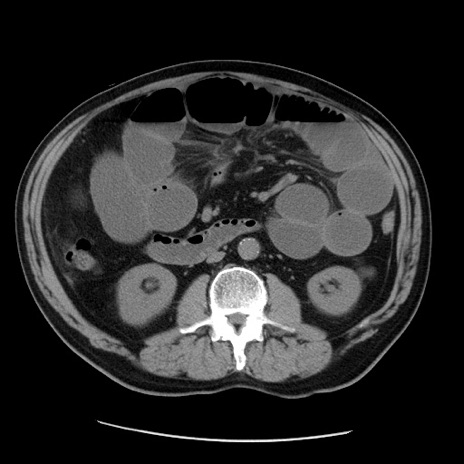

症例20(横断像)

【症例】 60歳代男性

【主訴】 腹部膨満、嘔吐

【現病歴】5日前頃より倦怠感を認め食事量減少し4日前の朝嘔吐、食事摂取困難となった。 3日前近医受診し点滴施行され整腸剤などを処方された。 当日他院を受診し、腹部膨満著明、炎症反応の上昇(CRP10.8、WBC11200)あり、紹介受診となる。

【身体所見】 意識JCS1 受け答えがはっきりしないBP 111/57mHg、 P 67bpm、、BT35.2°C、SpO2 97%(RA)、 腹部:膨隆、打診で鼓音あり、全体的に圧痛有り、腸蠕動音(-)、反跳痛ははっきりせず。

【データ】WBC 11400、CRP 14.20